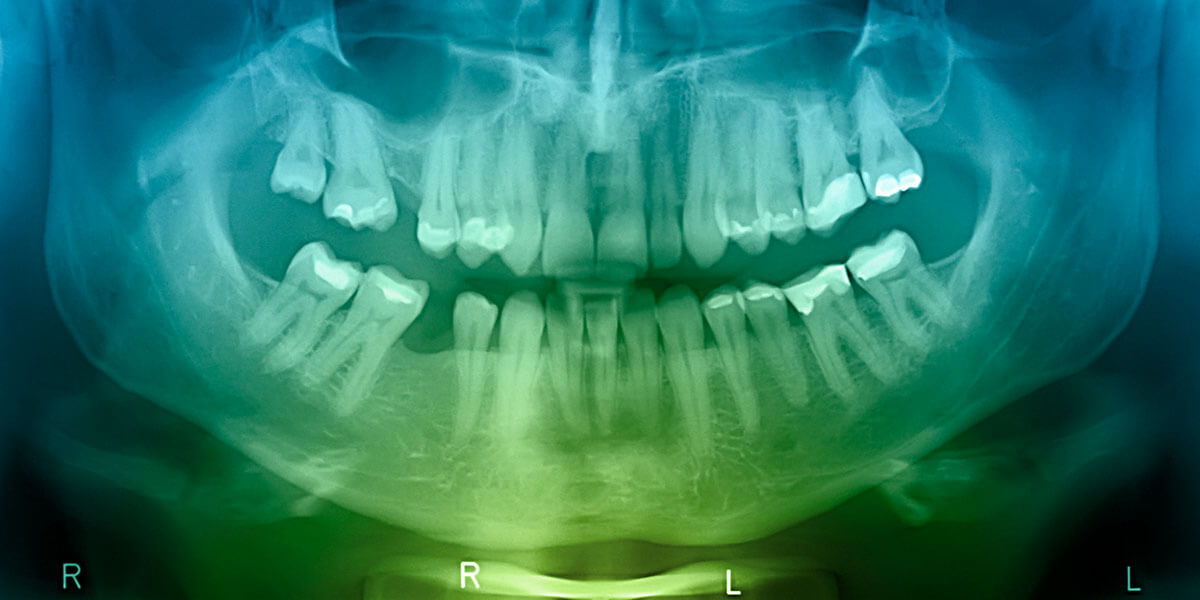

Digital X-Ray

Digital x-rays reduce the amount of radiation needed as compared to film x-rays. The improved diagnostic capability of digital x-rays and the ability to view the x-rays on a computer screen allow the patient to better understand and follow treatment. Digital x-rays are instant, there is no longer a need to develop the film. Digital x-rays save time and increase patient care. It’s also a very green technology. By eliminating film, developer and chemical waste it is better for you and the environment!